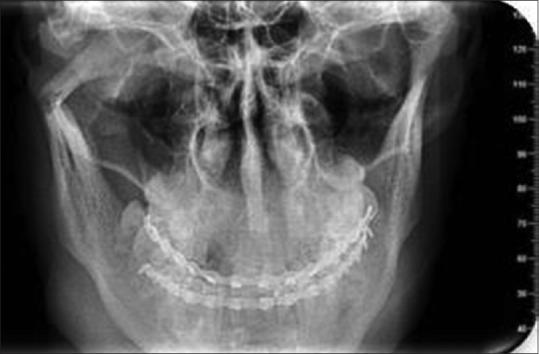

This randomized prospective study was conducted on thirty patients who visited the Department of Oral and Maxillofacial Surgery, Government Dental College, Srinagar, with condylar fractures. All fractures were displaced; either angulated between 10° and 45° and the ascending ramus was shortened by >2 mm to <15 mm. Patients were divided into two groups after satisfying the inclusion and exclusion criteria - Group I (closed treatment) and Group II (open reduction) (15 implants in each group). In Group I, patients were treated by mandibulo-maxillary fixation using arch bar and elastics for 4 weeks, and in Group II, patients were treated by ORIF using two 1.5-mm miniplates. Follow-up was done at 1 month, 3 months, and 6 months. Our postoperative evaluation included five parameters - maximal interincisal opening, protrusion, lateral excursion on fractured and nonfractured sides, anatomical reduction, and pain and malocclusion. Nonparametric data were compared for statistical significance with Chi square test and parametric data with an independent sample's -test ( < 0.05).

本随机前瞻性研究针对30例因髁突骨折就诊于斯利那加政府牙科学院口腔颌面外科的患者开展。所有骨折均有移位;成角10°至45°,升支缩短>2mm至<15mm。满足纳入和排除标准后,患者被分为两组——第一组(闭合治疗)和第二组(切开复位)(每组15例)。第一组患者采用牙弓夹板和弹力牵引进行下颌-上颌固定治疗4周,第二组患者采用两个1.5mm微型钢板进行切开复位内固定术治疗。在1个月、3个月和6个月进行随访。我们的术后评估包括五个参数——最大切牙间开口度、前伸、骨折侧和非骨折侧的侧向运动、解剖复位以及疼痛和咬合紊乱。非参数数据采用卡方检验比较统计学显著性,参数数据采用独立样本t检验(P<0.05)。